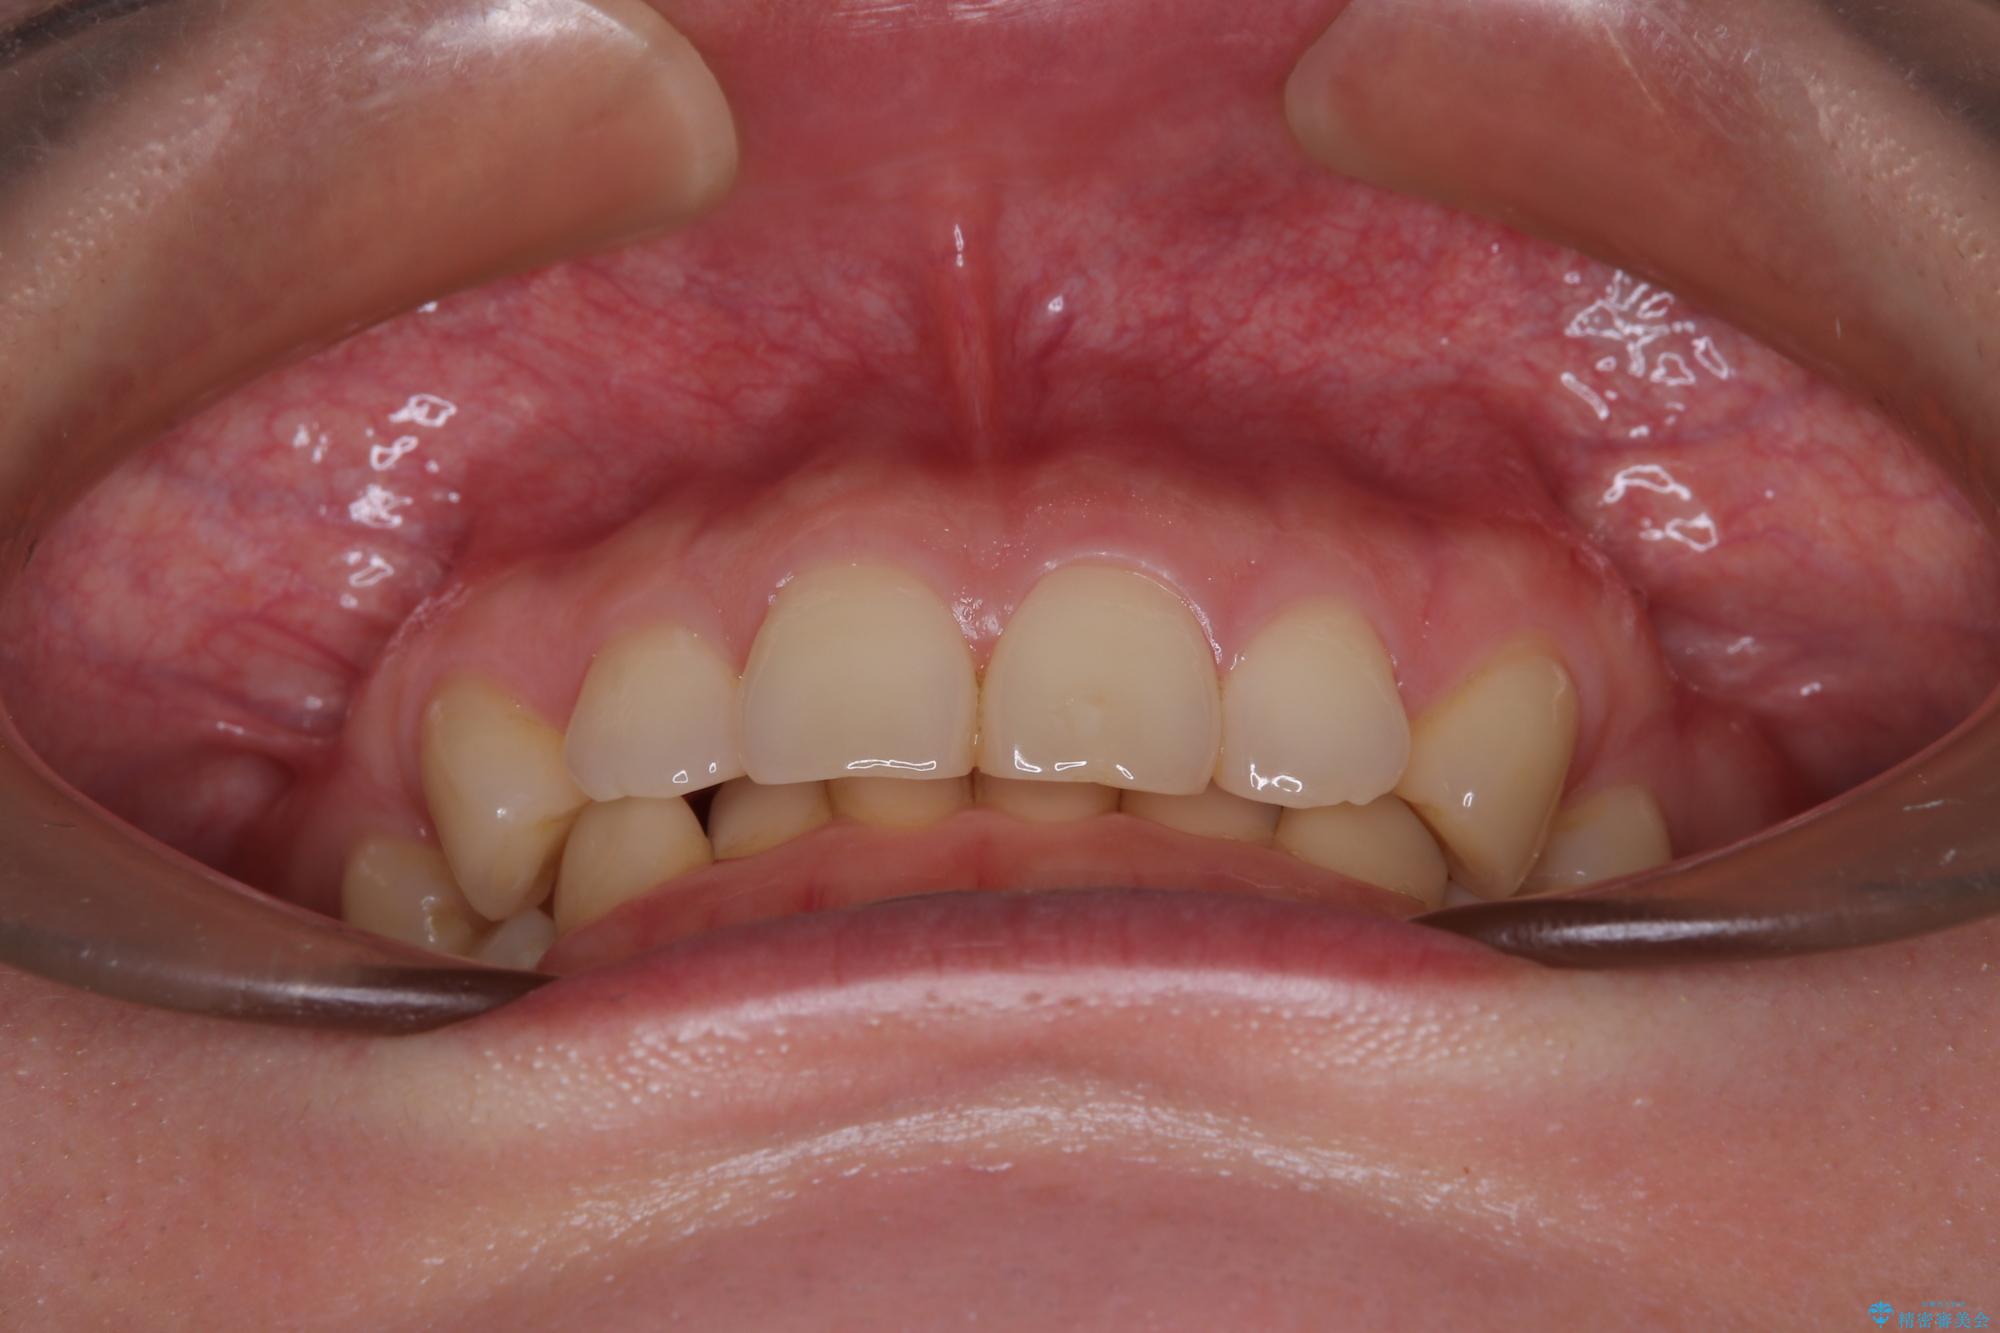

- 下顎前歯が完全に隠れてしまっていることを気にして来院された患者様です。

下顎の臼歯が手前に傾斜していることで咬み合わせが深くなってしまい、下顎前歯が見えないほどに上顎前歯が覆い被さっている状態でした。